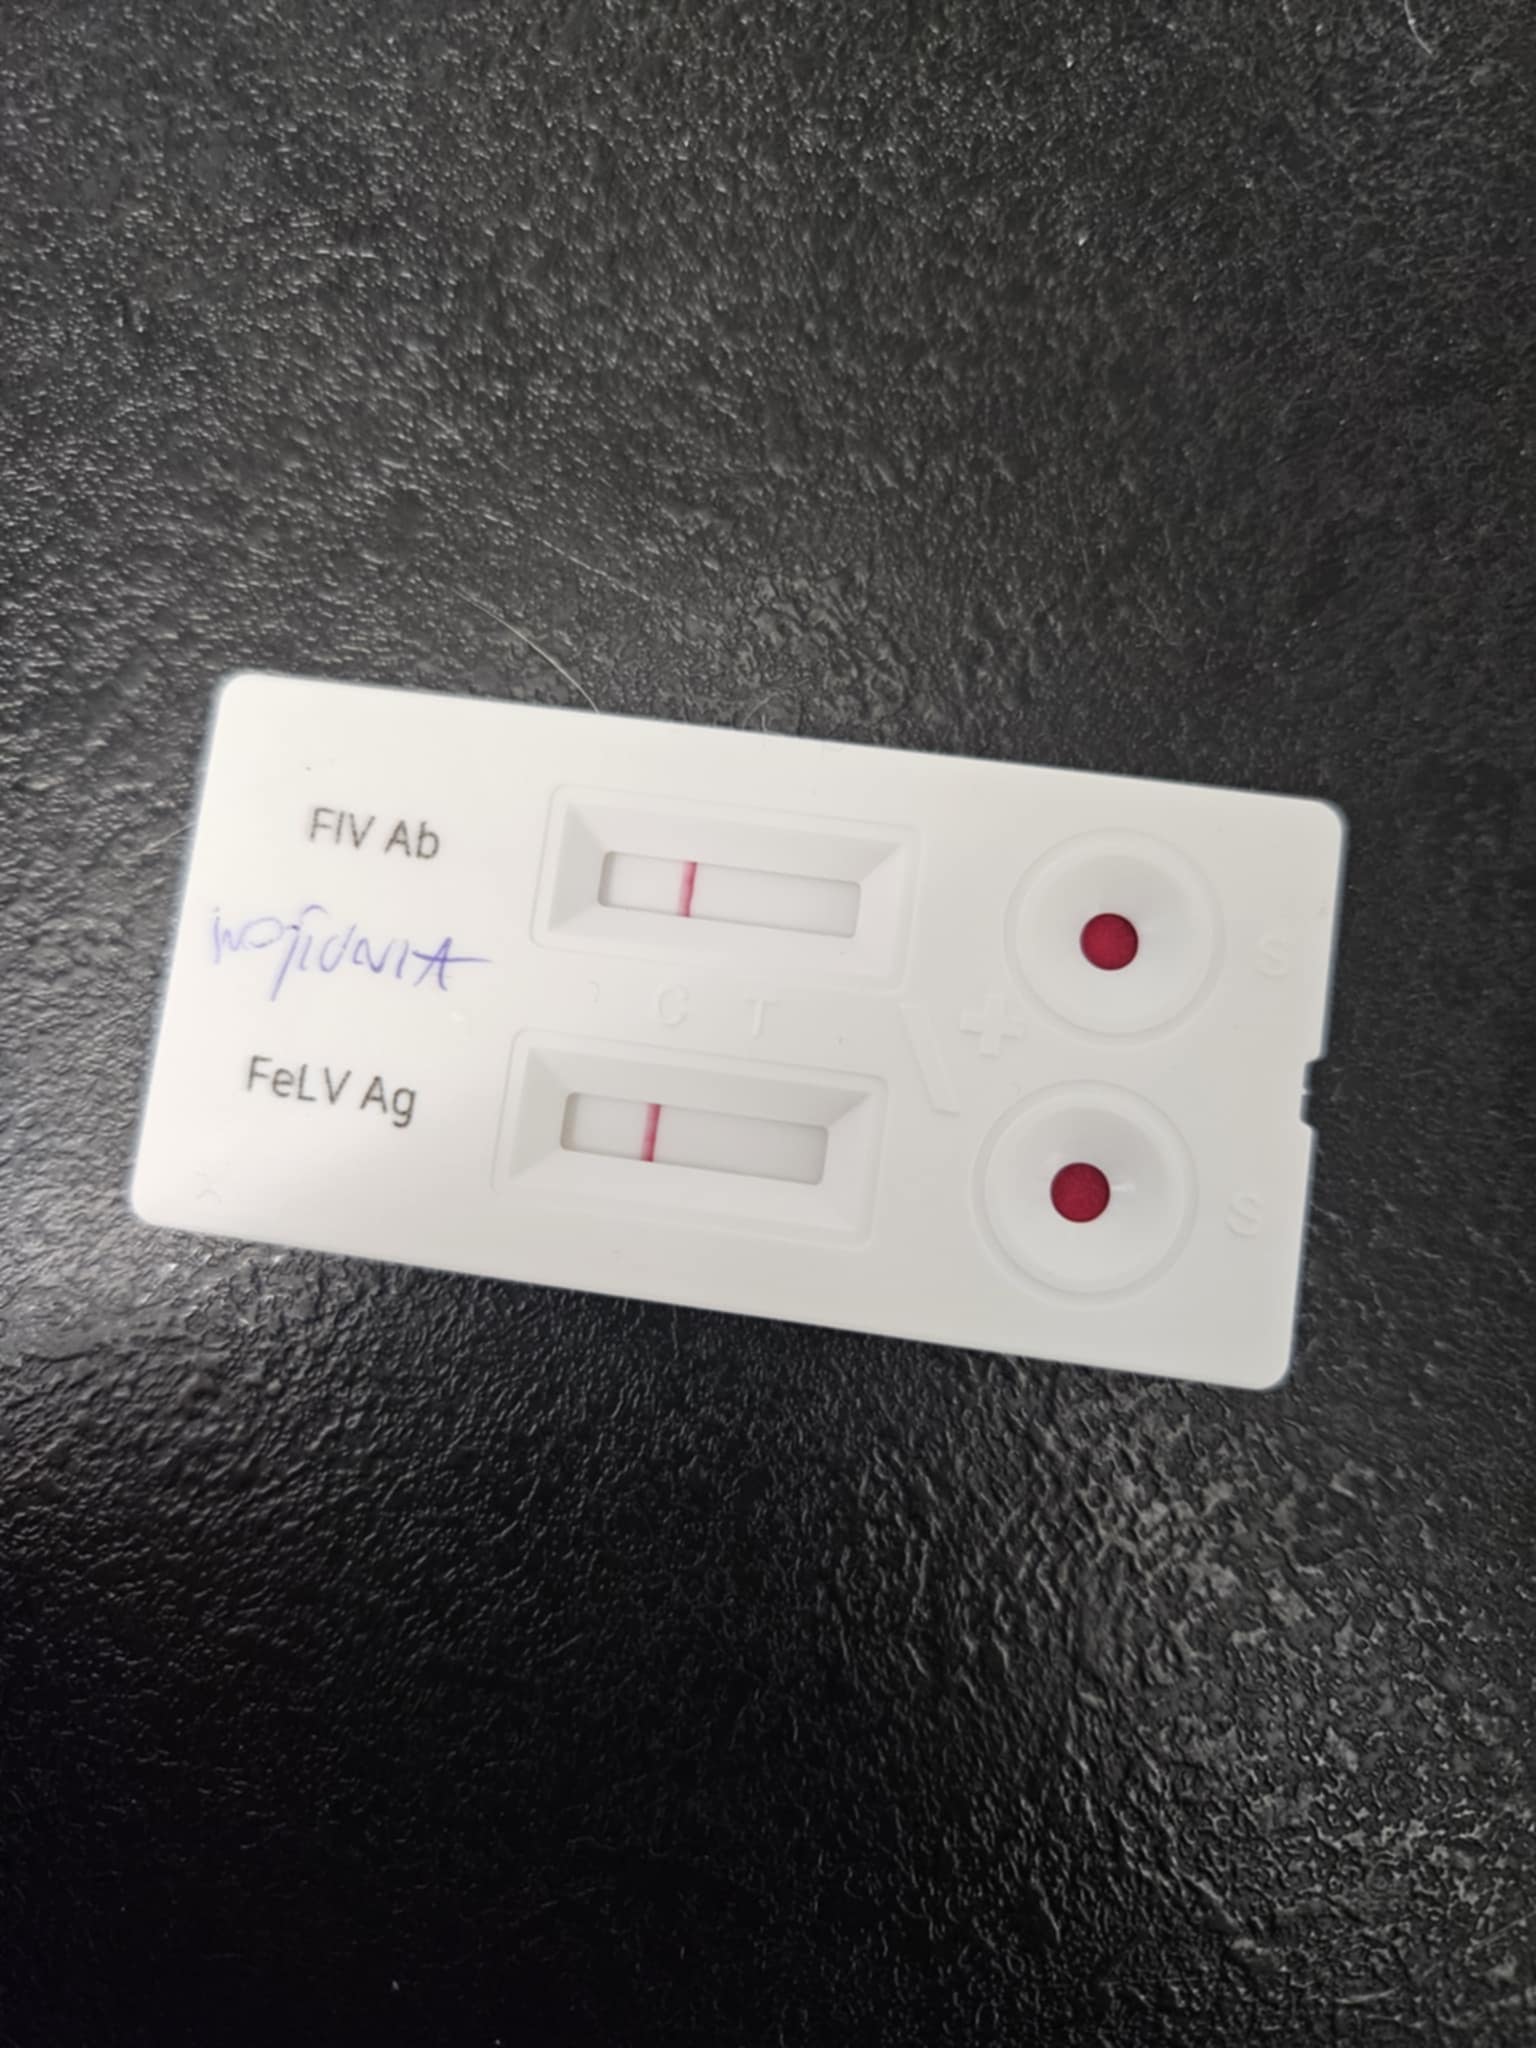

Wykonaliśmy malutkiej badania krwi, testy FIV/FELV. Koteczka ma trochę podwyższone leukocyty. Będziemy monitorować ten parametr.

- opłacenie pierwszej wizyty Wojtusi u weta (w tym badanie krwi, testy FIV/FELV, zdjęcia RTG w sedacji - około 600 zł